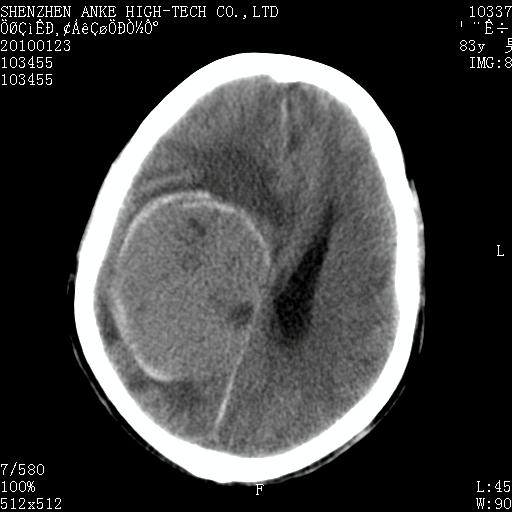

患者:男,83岁,突发意思不清2天。原有脑梗塞病史。

肿瘤卒中,考虑恶性,依次淋巴瘤、转移瘤、恶性脑膜瘤、胶质母等,建议mri。

肿瘤卒中,考虑恶性脑膜瘤可能性大。

脑膜瘤多见于老年女性,与雌激素水平有关。本例虽为老年男性,但是本例还是考虑脑膜瘤的可能性大。

镰旁脑膜瘤卒中